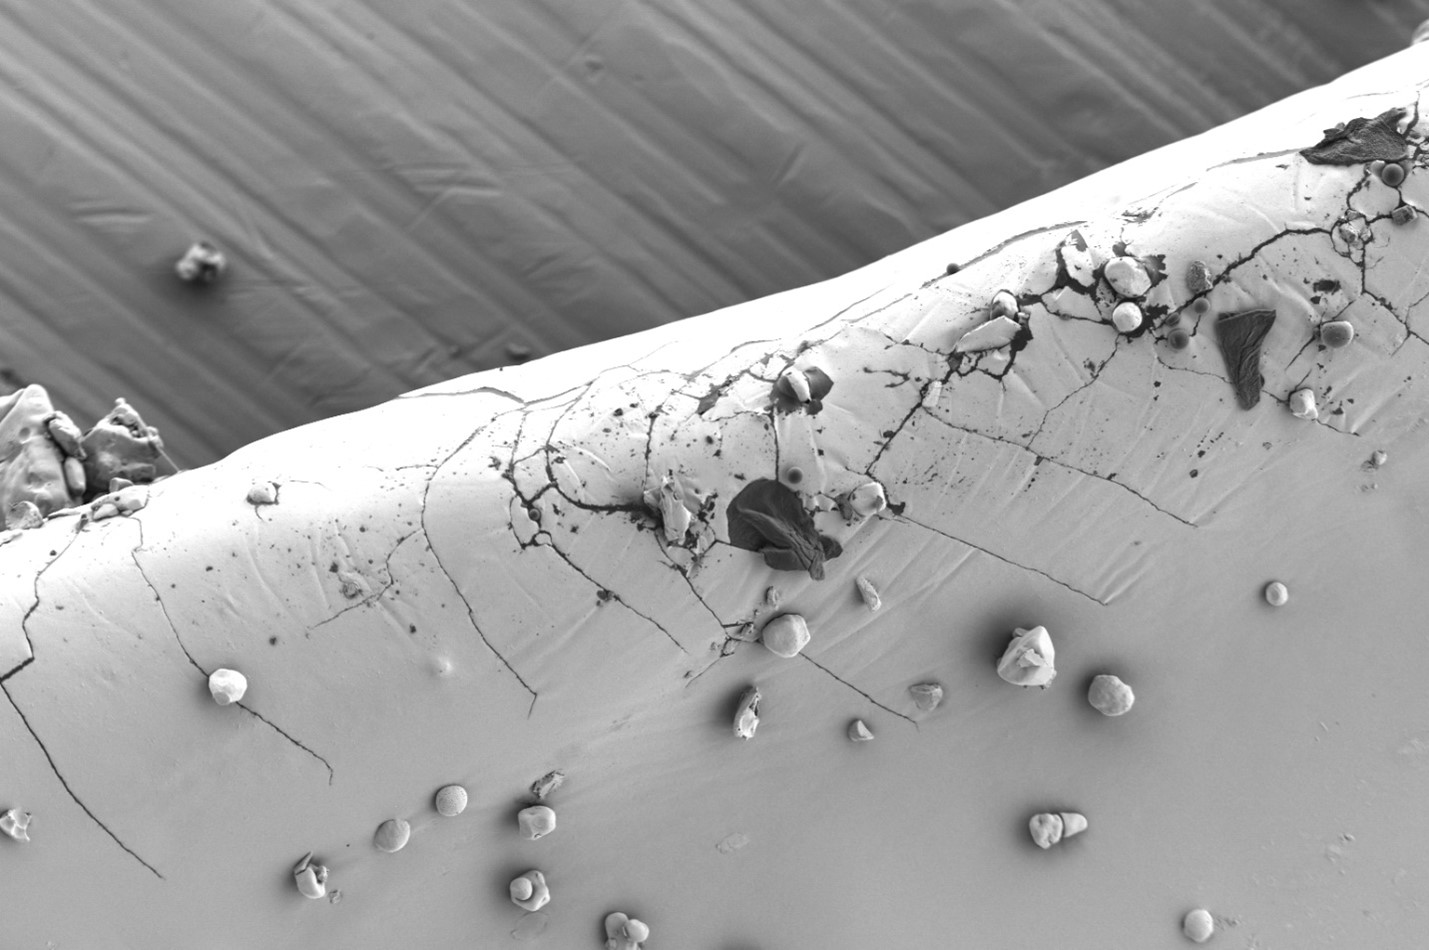

Так, при плановой проверке качества капсул с сульфатом глюкозамина с помощью оптического микроскопа были обнаружены мелкие дефекты на поверхности. Последующий анализ на СЭМ при высоком увеличении выявил микротрещины и прикрепленные пластинчатые частицы неправильной формы (рис. 1а). Морфология трещин указывала на их возможное происхождение в результате коррозии под напряжением, связанной с неравномерной сушкой покрытия и релаксацией полимерных напряжений. Инородные частицы по своей структуре (рис. 1b — чистая поверхность) отличались от матрицы капсулы.

Сопоставление с типичными микроорганизмами позволило исключить биологическую природу загрязнения; наиболее вероятным источником была признана неорганическая пыль из производственной среды или вспомогательных веществ. Эти данные послужили основой для корректировки режимов нанесения покрытия и ужесточения контроля чистоты в производственных помещениях.

Рис. 1а — Поверхность капсулы с сульфатом глюкозамина: визуализированы пластинчатые включения и микротрещины; загрязнения проникают в трещины. Изображения получены с помощью микроскопа LANSEM 30.